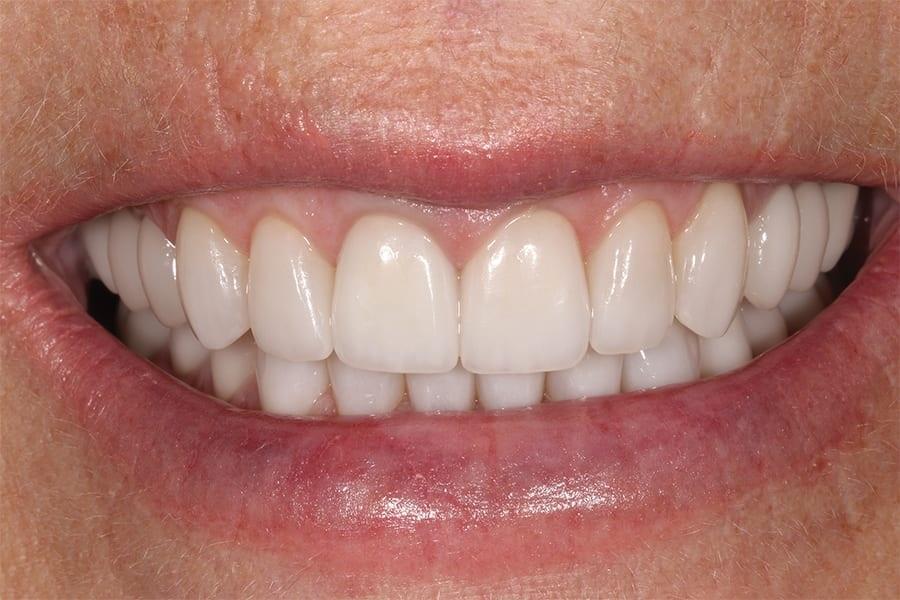

Разделение лечения на этапы в течение 18 месяцев позволило пациентке пройти полную реабилитацию полости рта без значительной одномоментной финансовой нагрузки. Результат превзошел ожидания пациентки, и она была полностью удовлетворена своей новой улыбкой (фото 12–16). При контрольном осмотре через 6 месяцев все реставрации оставались интактными, без сколов и разрушений, при этом пациентка отмечала комфортную окклюзию.

Фото 14. Вид с ретракторами после лечения, демонстрирующий окончательные реставрации нижней челюсти и выравнивание зубной дуги.

Фото 16. Окклюзионный вид нижней челюсти после лечения, демонстрирующий перекрытие зон прежнего износа.